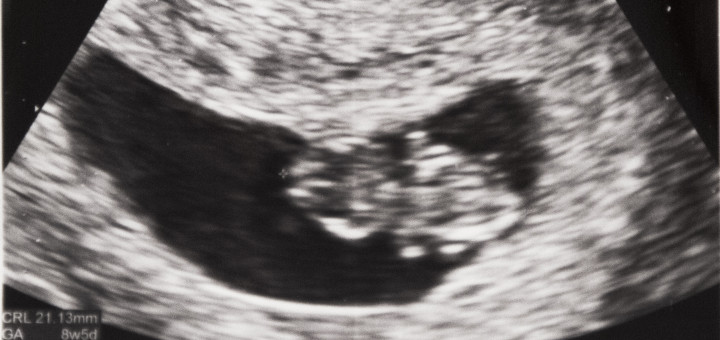

Baby Rez is growing big. My belly feels huge; if I’m already this big, I’m wondering how giant I’ll be at 9 months. We had a doctor appointment last week and Dr. Karl said “You’re almost at the third trimester.” I was like “whaaaat? I thought the third trimester started...